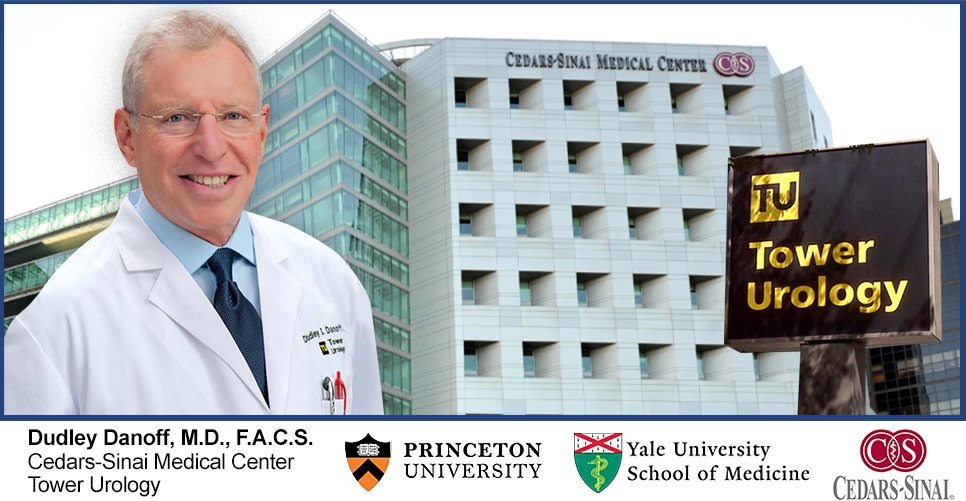

America’s Leanding Urologist Strongly Recomends Prostadine to All Men!